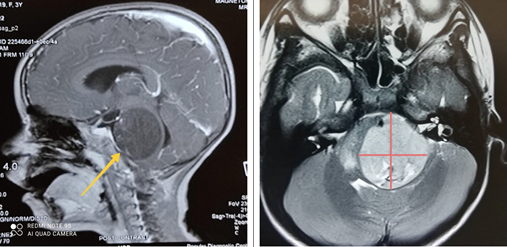

In our patient cohort, only 8 individuals underwent surgical intervention, and adequate tissue for pathological examination was obtained from 6 of them. Table 3 shows the variety of pathological types of gliomas (Figure 1).

Figure 1 MRI findings show a fairly large (4cm x 4cm) expansile rounded lesion in the brainstem involving the pons and midbrain, with triventricular hydrocephalus.